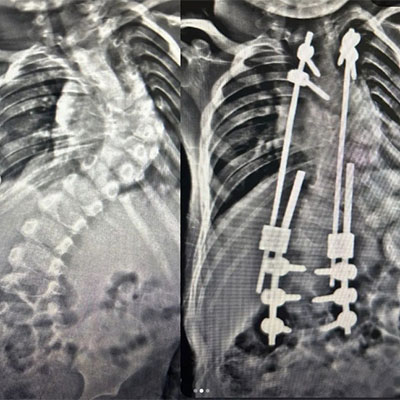

Revizyon Ameliyatı

Erken başlangıç gösteren skolyozlarda ve konjenital (doğumsal ) skolyozlarda tekrar gerektiren operasyonlar yapılır. Ayrıca enfeksiyon, enstrüman (implant ) hataları, psödoartroz (kaynama sorunları )ya da tamamlanmamış cerrahi işlem durumlarında revizyon cerrahisi uygulanmalıdır.Yani; mekanik sorunlar,komplikasyonlar,enfeksiyon ve zaman içinde gelişen büyüme yada yaşlanma sorunları nediyle revizyon gerektiren skolyoz ve kifoz hastalarına kliniğimizde tecrübeli ekip dahilinde cerrahi müdahaleler gerçekleştirilmektedir .